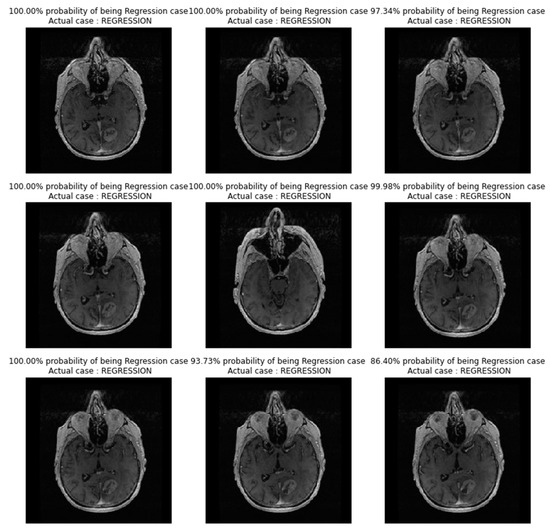

In Figure 7, images showing actual cases versus the predicted cases, with the probability of prediction, for the TL_model on unseen images, are presented.

Figure 7. Images showing actual cases versus the predicted cases, with probability of prediction, for the TL_model on unseen images.